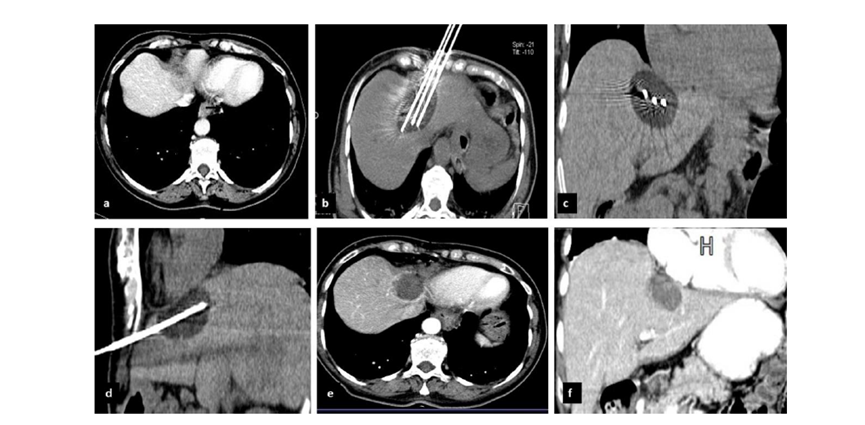

(A)動脈期CT圖像顯示有一個包膜下結(jié)節(jié)(箭頭)。(B)門靜脈期CT圖像顯示病灶區(qū)(箭頭)。(C) 在手術(shù)過程中的CT顯示一個冷凍探針位于病灶內(nèi)。(D)消融后,術(shù)后1個月影像CT顯示完全消融。患者在手術(shù)及住院期間無并發(fā)癥及重大并發(fā)癥發(fā)生。隨訪時間中位數(shù)為7個月(范圍:3-12個月),隨訪期間患者無局部腫瘤進展或死亡。

膽囊附近轉(zhuǎn)移灶(來自子宮頸癌)的冷凍消融術(shù)(A)門靜脈期 CT 圖像顯示膽囊附近有病變(箭頭)。(C) 手術(shù)過程中CT 顯示冷凍探針位于病灶內(nèi)。(D)消融手術(shù)后 1 個月CT 顯示完全消融。

CT引導(dǎo)的冷凍消融

(b) 冷凍消融術(shù)中影像顯示冰球完全覆蓋病變。(c) 19個月后隨訪,沒有發(fā)生局部腫瘤進展。完全消融率為97%(66/68);2名患者均接受了額外的冷凍消融,隨后實現(xiàn)完全消融。平均隨訪期為 12.8 個月(范圍:3-27 個月)。所有患者均接受影像復(fù)查(CT 或 MRI)。11個病灶(16.2%)檢測到局部腫瘤進展,6、12和18個月時的累積局部腫瘤進展率分別為4%、8.2%和20.5%。8例出現(xiàn)遠(yuǎn)處肝內(nèi)或肝外病變的患者接受經(jīng)動脈化療栓塞、經(jīng)動脈化療栓塞加射頻消融治療或全身化療。